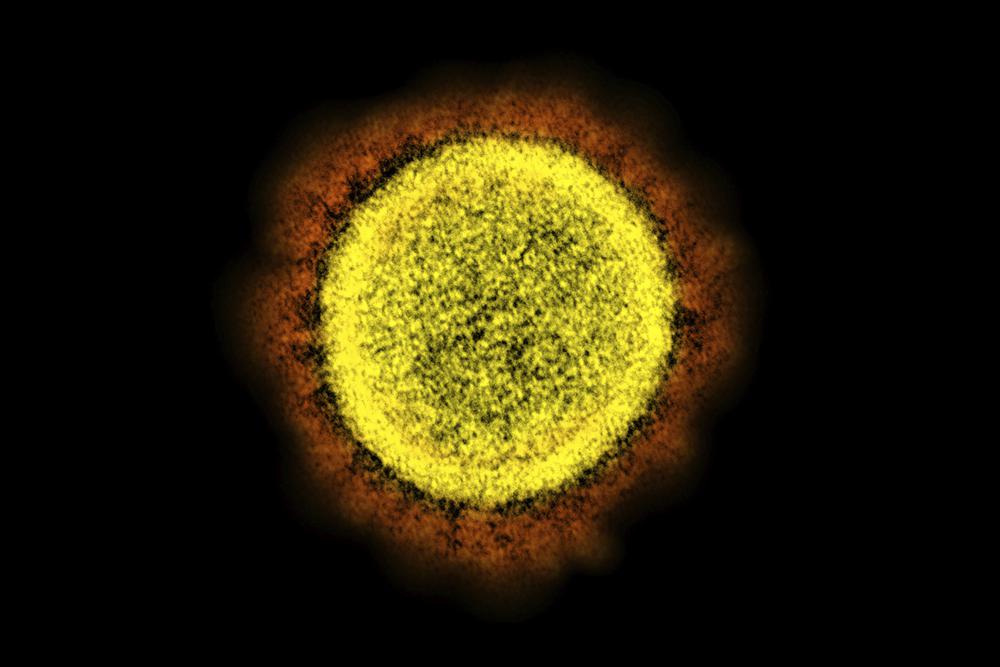

FILE - This 2020 electron microscope image made available by the National Institute of Allergy and Infectious Diseases shows a Novel Coronavirus SARS-CoV-2 particle isolated from a patient, in a laboratory in Fort Detrick, Md. The coronavirus mutant widely known as stealth omicron is now causing more than a third of new omicron cases around the world. But scientists still don�t know how it could affect the future of the pandemic. (NIAID/NIH via AP, File)

The coronavirus mutant widely known as �stealth omicron� is now causing more than a third of new omicron cases around the world, but scientists still don�t know how it could affect the future of the pandemic.

Researchers are slowly revealing clues about the strain, a descendant of omicron known as BA.2, while warily watching it become ever more prevalent.